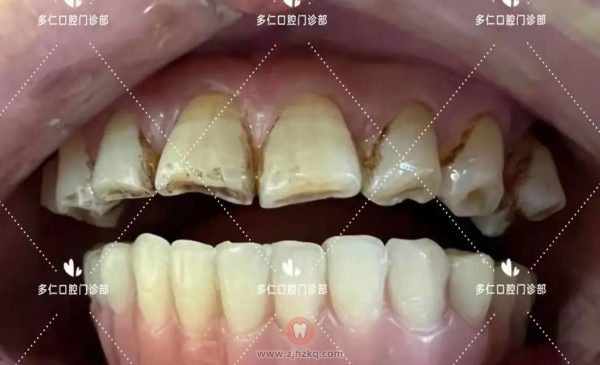

即刻修复义齿

即刻修复完成15:30

即刻修复后口内照

当天种牙,当天得牙。做完即刻修复的叔叔及陪同朋友都非常满意。